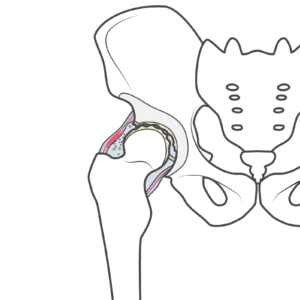

股関節 【葛飾区金町のやぎはし整体院】股関節と大腰筋の関係 股関節の前面の筋肉が股関節痛を出す《金町のやぎはし整体院が解説》 分冊解剖学アトラス 第5版より改編して掲載 股関節の前面に、「腸腰筋」「大腿直筋」と呼ばれる筋肉があります。 これはもも上げなど、足を前に出す時に使われる筋肉です。 この「腸腰筋」「大腿直筋」に負担がかかり、炎症が起きたり筋肉が硬くなったりすると、股関節...

股関節 【葛飾区金町のやぎはし整体院】手術しないで臼蓋形成不全を治す治療 手術しないで、臼蓋形成不全を治す方法とは?《金町のやぎはし整体院が解説》 骨盤の形態異常のことを指します。 先天性あるいは後天性に臼蓋が浅く、股関節が不安定な状態であることを言います。 股関節とは骨盤の臼蓋と大腿骨の大腿骨頭で関節を形成していますが、臼蓋形成不全の状態になりますと、股関節が不安定になるため、股関節周りの...